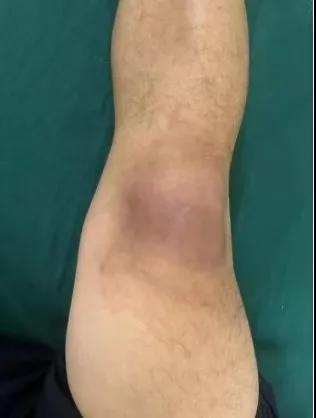

近日,漯河醫(yī)專二附院(漯河市骨科醫(yī)院、漯河市立醫(yī)院)手顯微外科(骨四科)李俊明主任團隊應用清熱解毒、拔毒生肌類中藥(骨炎膏)外用結(jié)合抗生素成功治愈一例膝關(guān)節(jié)外傷后軟組織感染病人。

患者,以“外傷致右膝紅腫、疼痛20余天”為主訴就診,20余天前,因騎電車摔傷右膝關(guān)節(jié),致使出現(xiàn)右膝腫脹、疼痛、活動受限,在當?shù)蒯t(yī)院給予消腫、止痛治療效果差,繼而出現(xiàn)膝關(guān)節(jié)紅腫熱痛癥狀,門診給予滑膜炎片及消腫止痛藥物治療癥狀未見好轉(zhuǎn),慕名前來我院手顯微外科住院。入院當天即給予中藥外敷(骨炎膏),穿刺膿性分泌物送細菌培養(yǎng),給予廣譜抗生素治療(細菌培養(yǎng)未出)。

中藥外敷(骨炎膏)主要適用于局部紅腫熱痛,四肢血栓形成、靜脈炎等,具有清熱解毒,拔毒生肌的作用。

中藥外敷骨炎膏給藥直接作用于病灶,彌補了單純口服藥物局部濃度不足的缺陷;同時,中藥外敷與抗生素的系統(tǒng)性抗感染形成"靶向-全身"雙重干預,可顯著縮短療程并降低耐藥風險,更為中西醫(yī)結(jié)合治療軟組織感染提供新的思路。(盧 闖 賈煒煒 劉 旭 袁錦鈺)